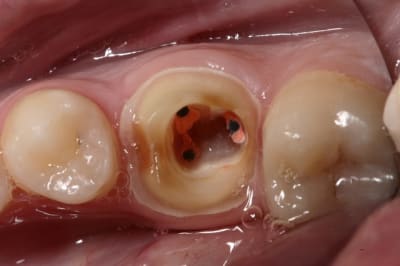

photo retrouvées :)

plus de place pour la ceramique, et plus de rétention dans l'endo que dans l'exo ;)